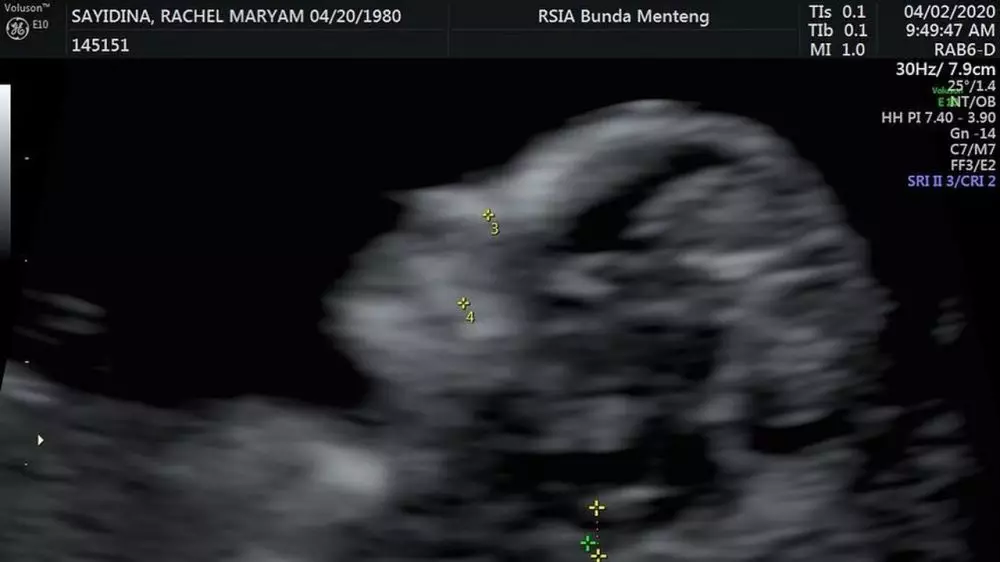

Pada usianya yang akan memasuki 40 tahun, Rachel Maryam kembali diberi anugerah mengandung buah hati yang kedua. Ini merupakan kehamilannya yang pertama bersama Edwin Aprihandono.

Ia pun mengunggah kabar bahagia ini dalam media sosial instagramnya @rachelmaryams. Ia pun mengunggah potret hasil USG pada janinnya yang saat itu baru berusia 12 minggu.